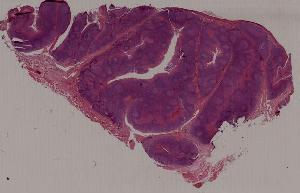

21.慢性扁桃体炎